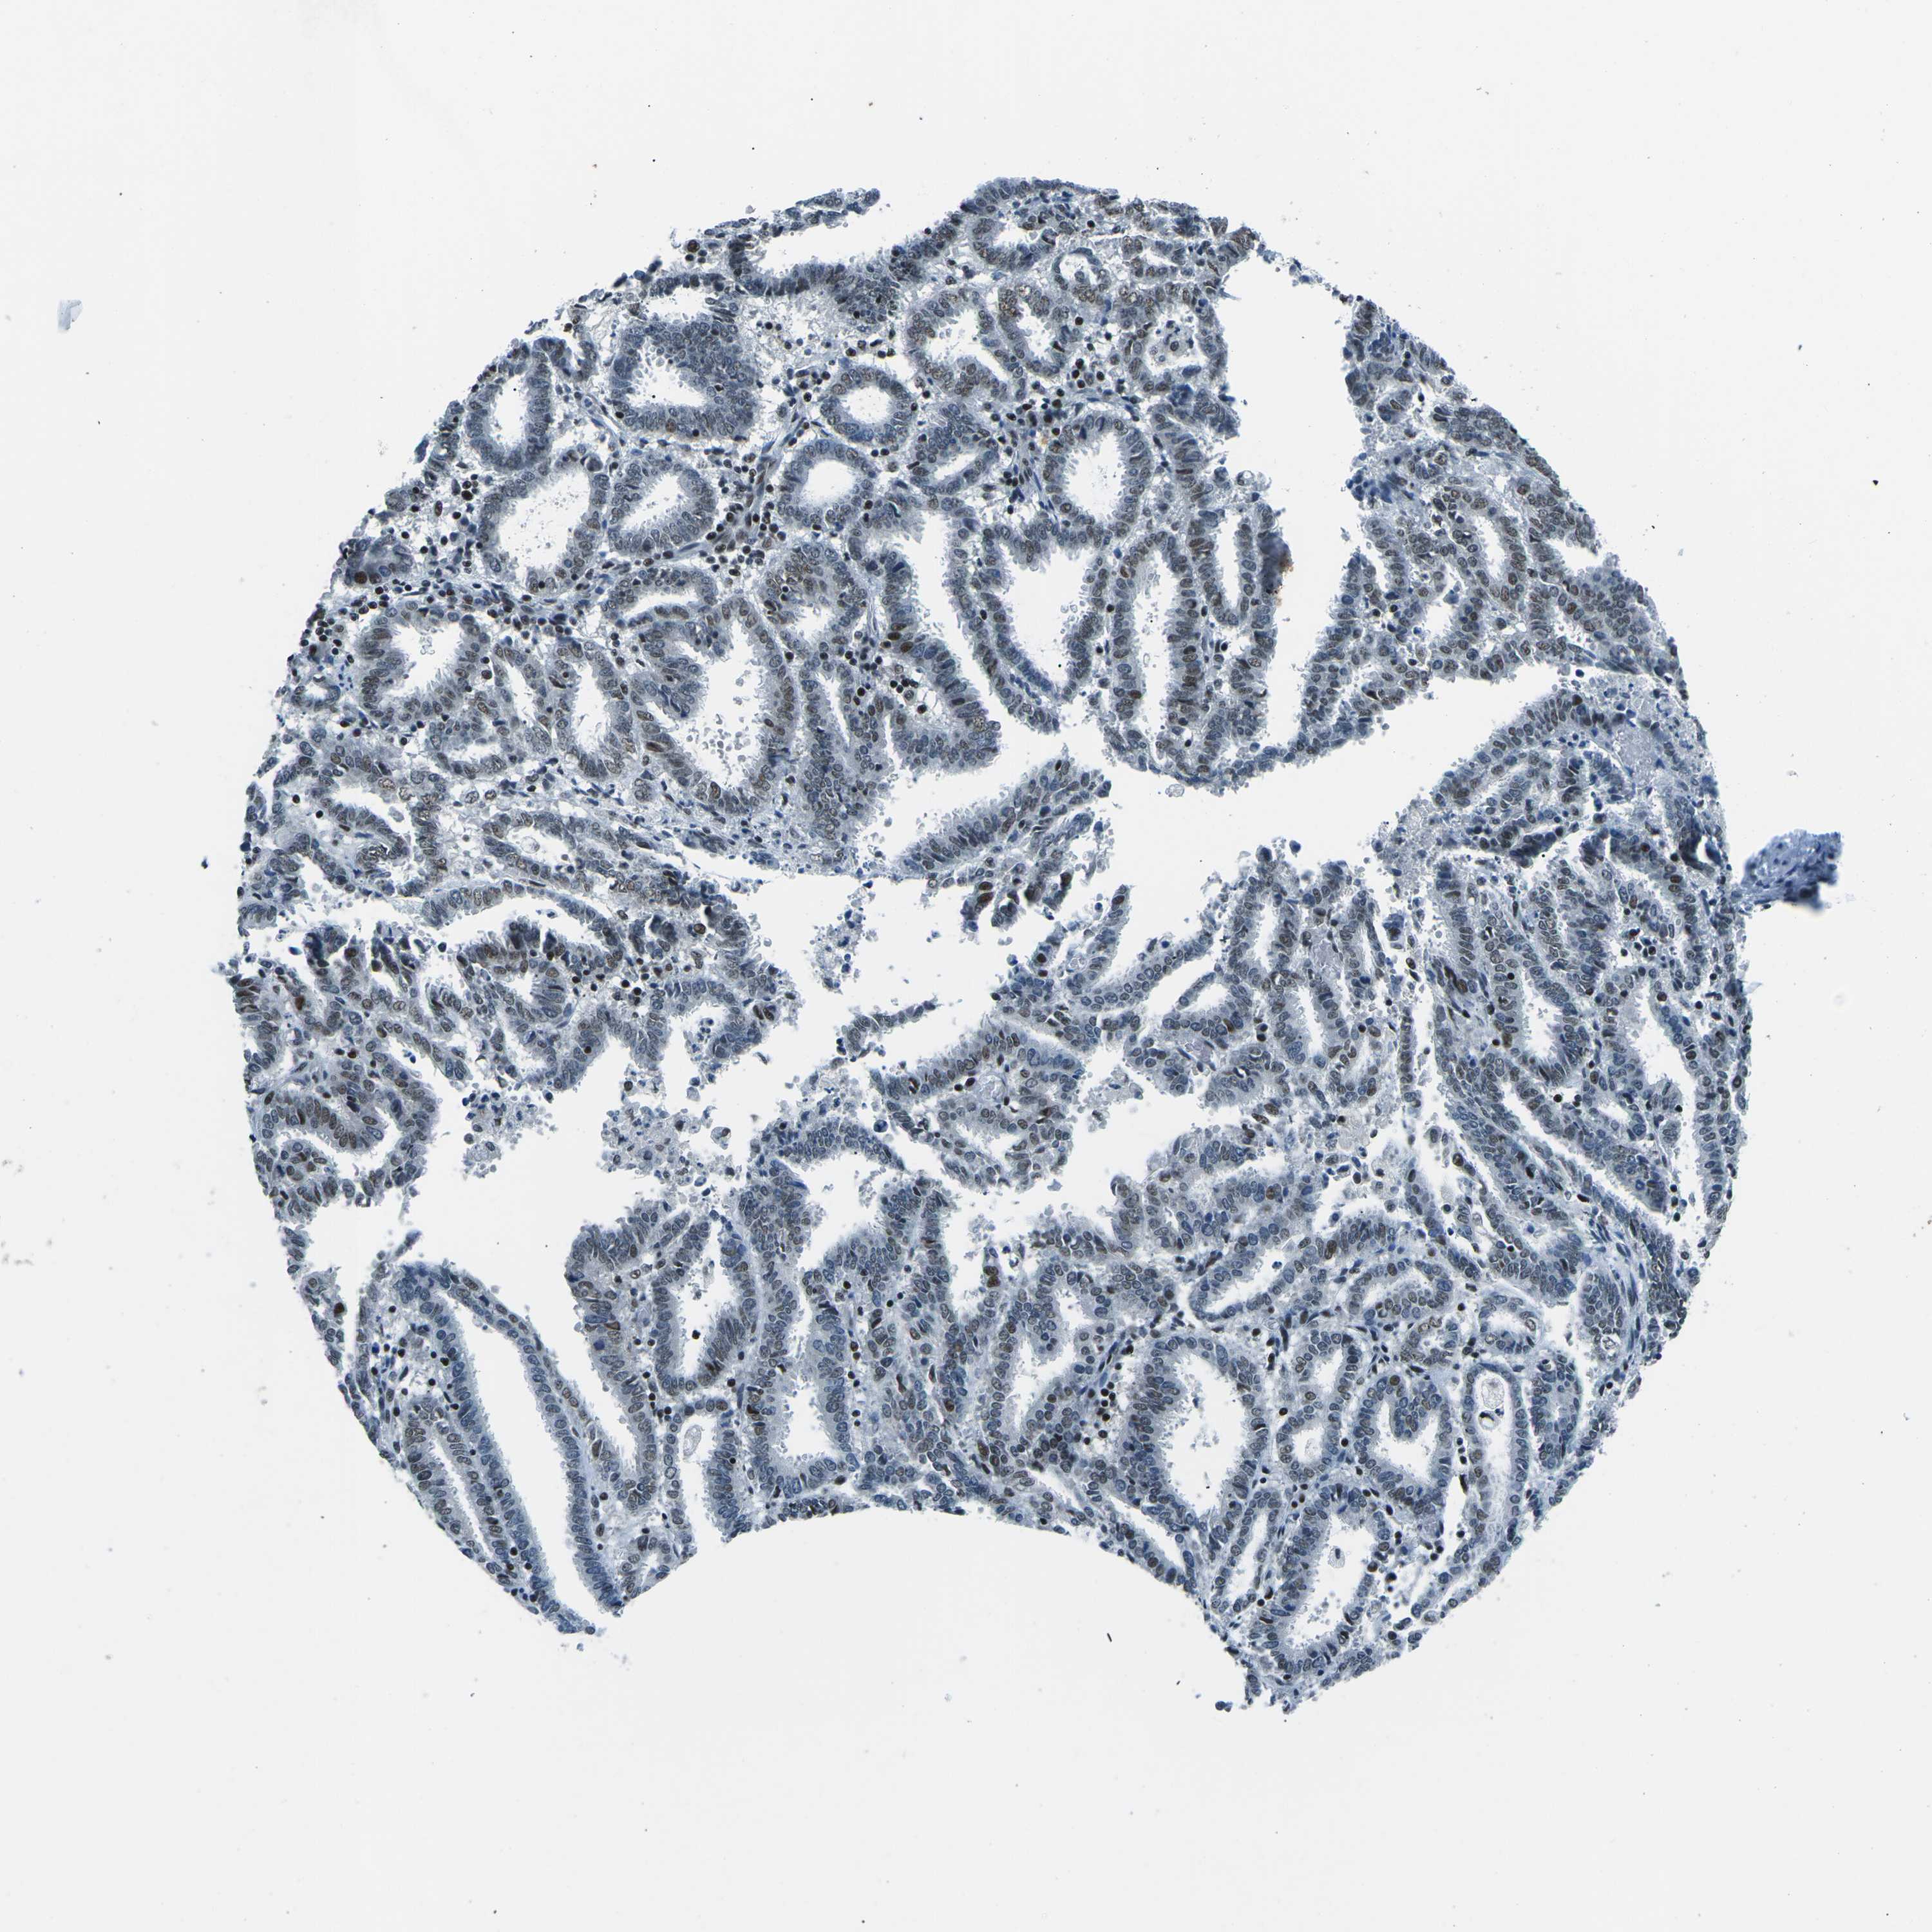

ENDOMETRIAL CANCER - Protein expressioni

A mouse-over function shows sample information and annotation data. Click on an image to view it in a full screen mode. Samples can be filtered based on level of antibody staining by selecting one or several of the following categories: high, medium, low and not detected. The assay and annotation is described here.

Note that samples used for immunohistochemistry by the Human Protein Atlas do not correspond to samples in the TCGA dataset.

Antibody stainingi

Antibody staining in the annotated cell types in the current human tissue is reported as not detected, low, medium, or high, based on conventional immunohistochemistry profiling in selected tissues. This score is based on the combination of the staining intensity and fraction of stained cells.

Each image is clickable and will lead to virtual microscopy that enables deeper exploration of all samples and also displays staining intensity scores, fraction scores and subcellular localization as well as patient and tissue information for each sample.

Antibody HPA019703

Antibody CAB016547

Staining

High

Medium

Low

Not detected

Intensity

Strong

Moderate

Weak

Negative

Quantity

>75%

75%-25%

<25%

None

Location

Nuclear

Cytoplasmic/membranous

Cytoplasmic/membranous,nuclear

Adenocarcinoma, NOS

Adenoma, NOS